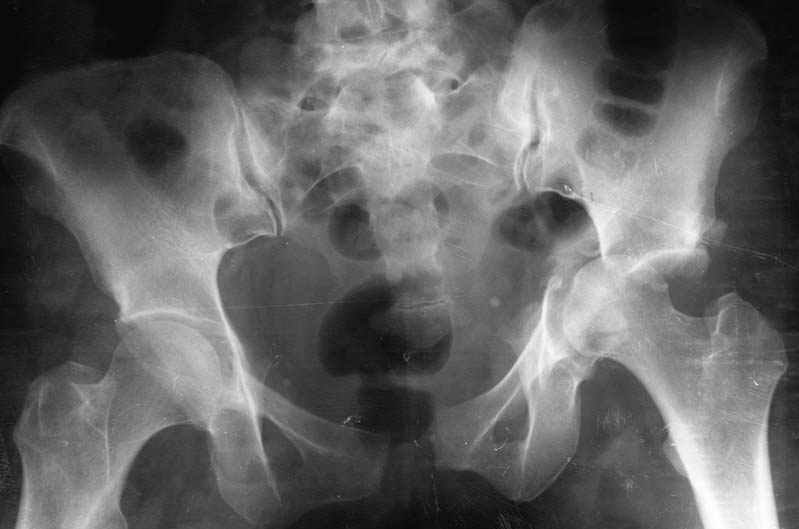

Мужчина, 34 года. Травма производственнная.

Какова ваша хирургическая тактика в подобном случае?

В день травмы - автономное скелетное вытяжекние (сдавление крыльев таза + дистракция бедра для спасения головки от острого края остатков свода), после стабилизации состояния синтез пластинами впадины и лона.